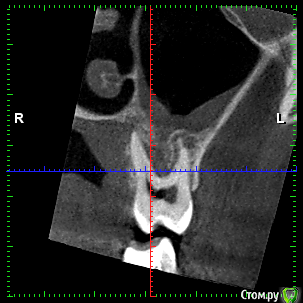

rezo47 Опубликовано 24 сентября, 2015 Автор Поделиться Опубликовано 24 сентября, 2015 Только пришло КТ, вопросов стало больше((( Ссылка на комментарий

kriokov Опубликовано 24 сентября, 2015 Поделиться Опубликовано 24 сентября, 2015 27 удаляйте Ссылка на комментарий

rezo47 Опубликовано 24 сентября, 2015 Автор Поделиться Опубликовано 24 сентября, 2015 (изменено) 27 удаляйтеДиагноз? Изменено 24 сентября, 2015 пользователем rezo47 Ссылка на комментарий

kladoffka Опубликовано 24 сентября, 2015 Поделиться Опубликовано 24 сентября, 2015 Хр пр 2 Ссылка на комментарий

kriokov Опубликовано 24 сентября, 2015 Поделиться Опубликовано 24 сентября, 2015 Диагноз?что хотите, на выбор(например- "не жилец" ) Ссылка на комментарий

red_butler Опубликовано 24 сентября, 2015 Поделиться Опубликовано 24 сентября, 2015 сначала гистология, потом лечение Ссылка на комментарий